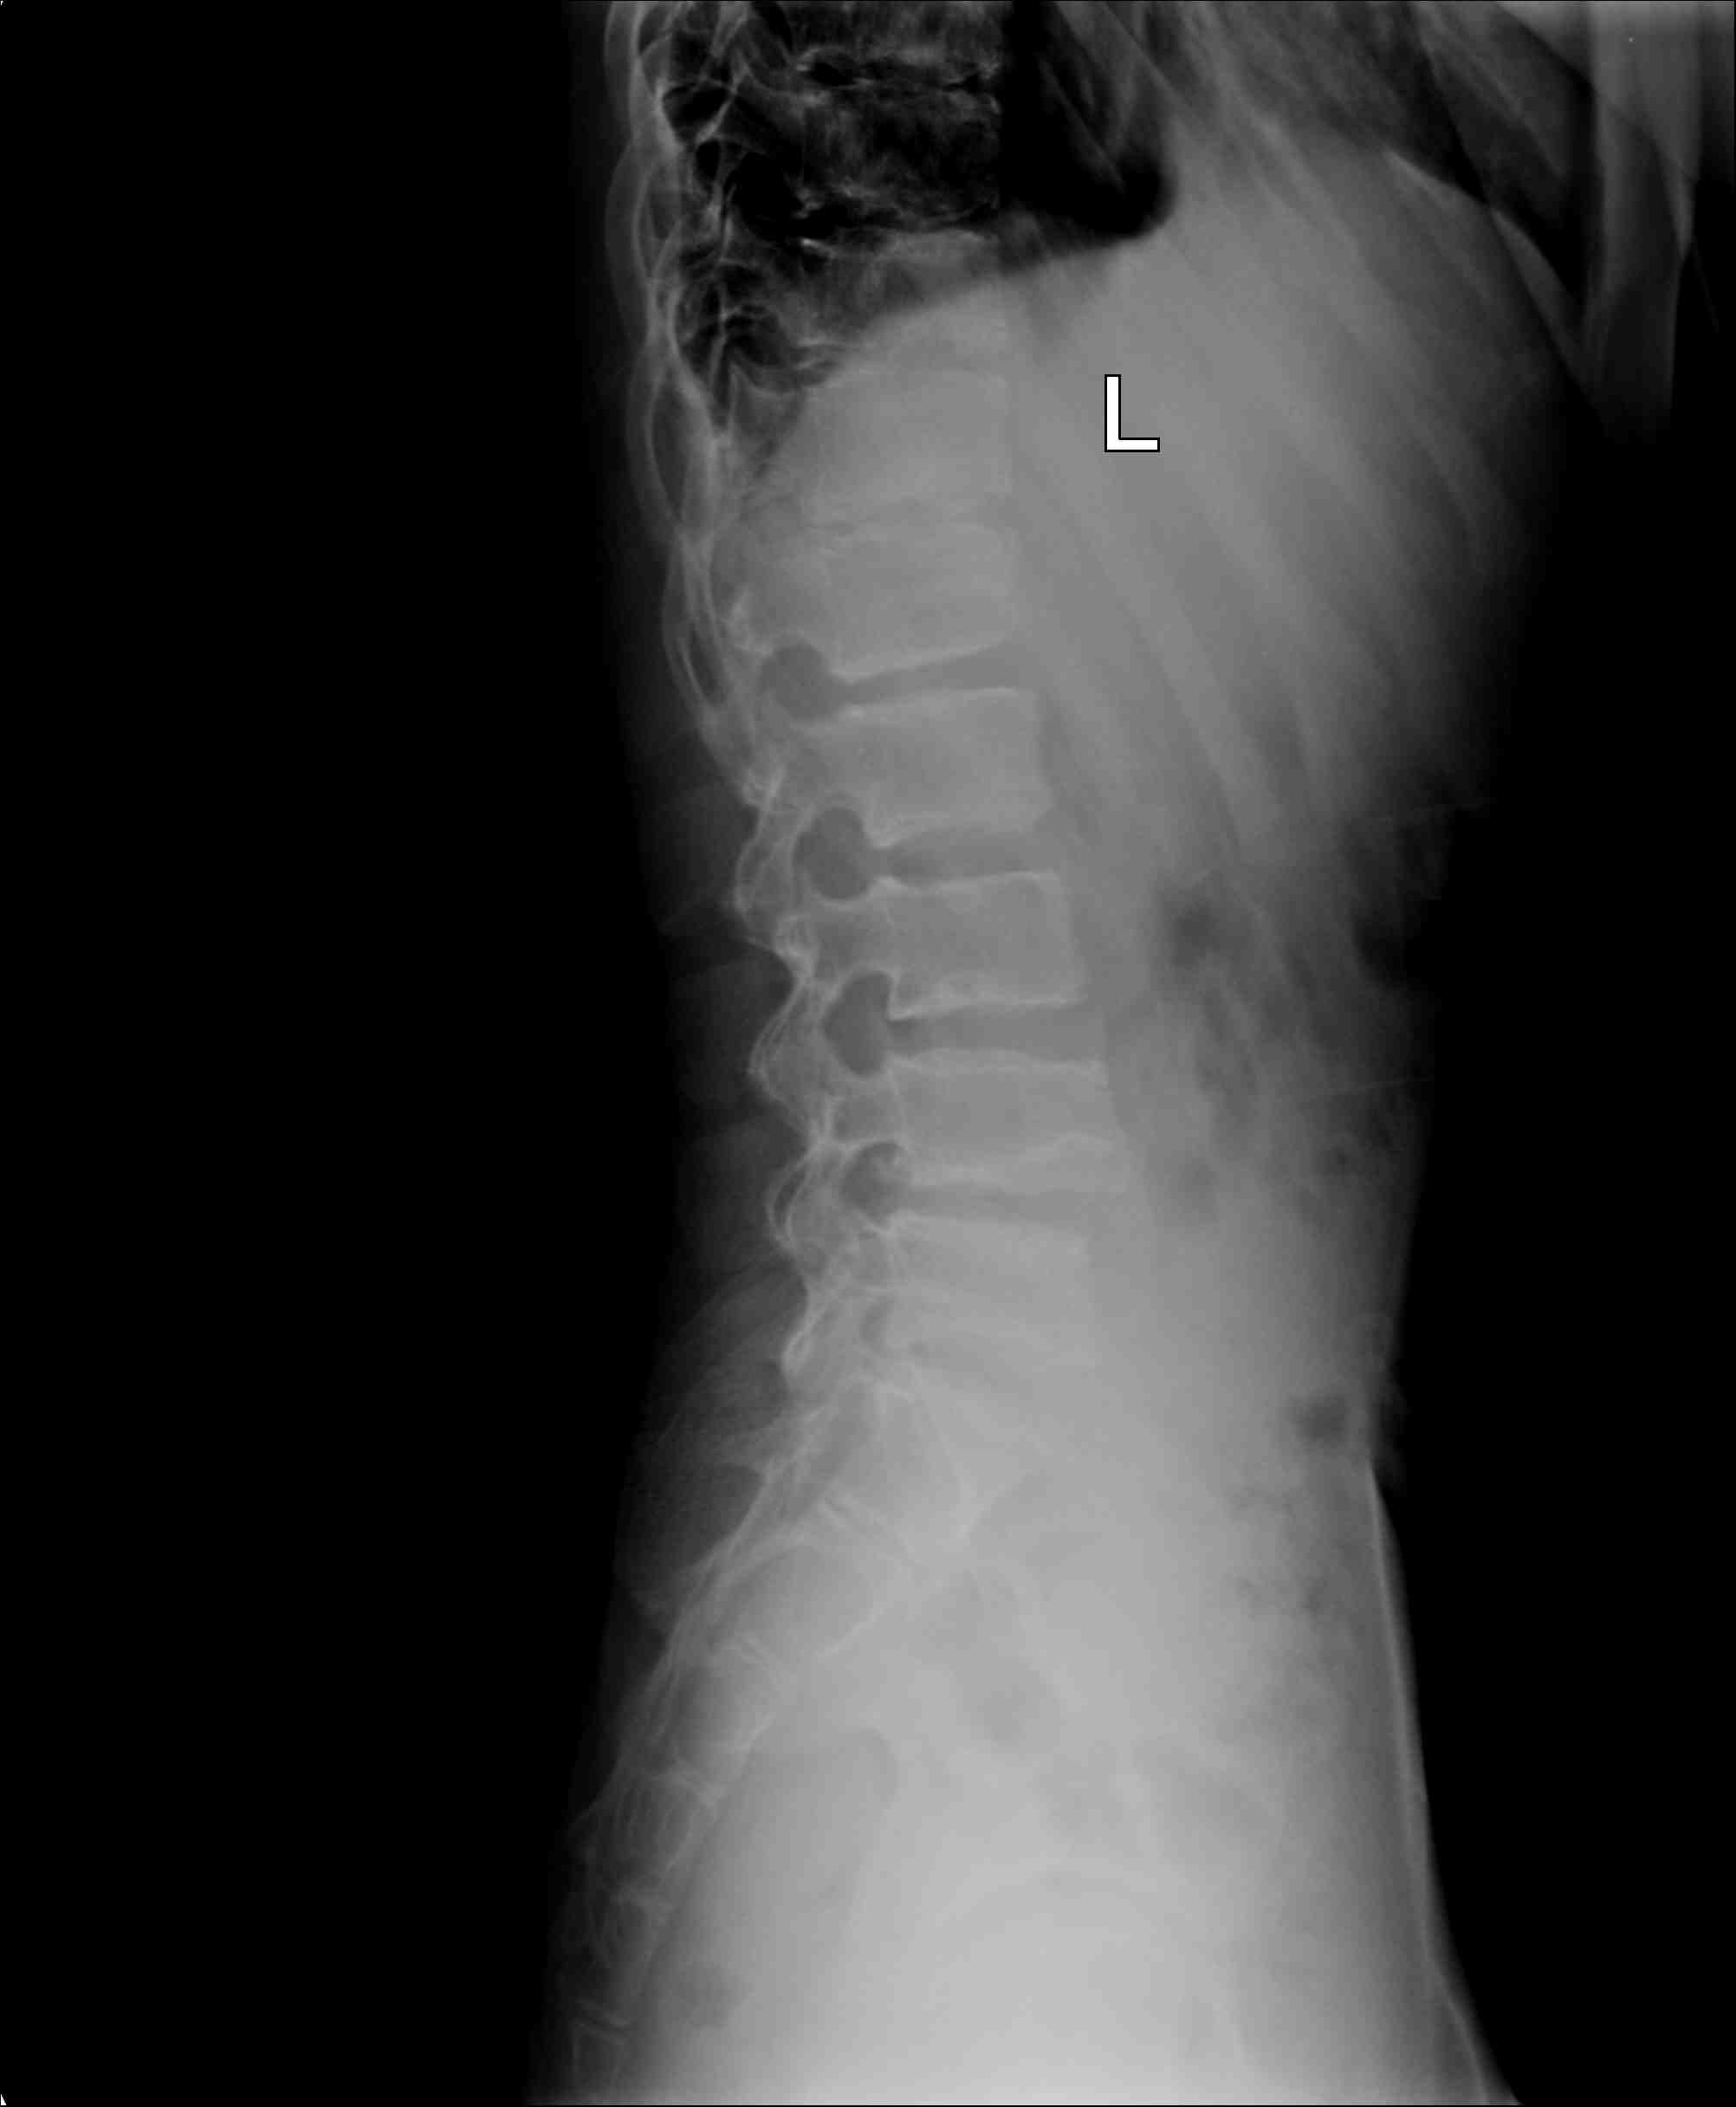

男 20岁 精神异常数年,摔倒后,腰背部疼痛,拍腰椎片。

scheuermann\"s病(休门氏病)即青少年脊柱圆背畸形。其发病原因尚不确定,男性多见,有家族性发病倾向。一 般认为与椎体的环行骨骺坏死有关。但有研究发现此骨骺与脊柱生长无关,不影响椎体的垂直生长,而且有患者在骨骺未出现前发病( 10 岁内)。本病的主要诊断依据为:青少年在胸椎中至少有 3 个相邻椎体有楔形变。x线显示胸椎中至少有3个相邻椎体有5 °或5 °以上的楔型改变,常伴有椎间隙变窄和schmorl 结节(许莫氏结节)。90% 的患者有椎体前后径增大。此病最常见的后凸位于胸椎,后凸顶点在中胸段。部分表现为胸、腰椎后凸,顶点位于胸腰段。患者出现后凸畸形的同时,可出现背痛,一般在停止生长后疼痛消失。若后凸加重并继发腰椎前凸加大,亦可出现下腰痛。